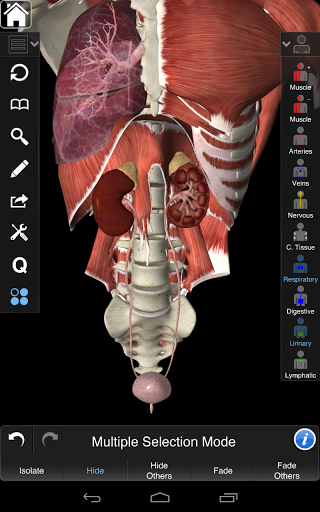

Cette application comprend l'anatomie essentielle pour 10 systèmes:

⁃Squelettique

⁃Muscles

⁃Tissu conjonctif

⁃Veines

⁃Artères

⁃Nerfs

⁃Respiratoire

⁃Digestif

⁃Urinaire

⁃Lymphatique

⁃ comprend également le cerveau et le cœur

La fonctionnalité intelligente trouvée dans l'application permet à l'utilisateur de dépouiller les couches de muscle via l'outil «scalpel». Cette application offre aux utilisateurs la possibilité d'activer / désactiver des systèmes sans avoir à désélectionner des structures individuelles ou à se frayer un chemin à travers une multitude d'onglets régionaux prédéfinis, comme d'autres applications.

---- Mode de sélection multiple - Masquer / Fondu / Isoler des structures individuelles ou multiples